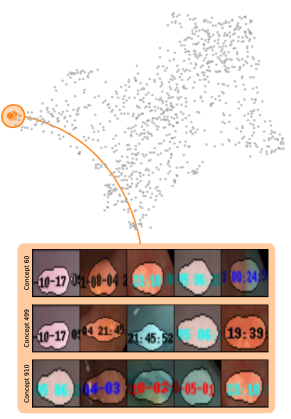

In contrast to detecting spurious samples, recent work focuses on identifying spurious model internals directly. This aligns with mechanistic interpretability, which seeks to decipher the internal mechanics of DNNs [56, 31, 13]. As outlined in Sec. 3.1, various global XAIs methods aim to explain the role of individual neurons, and these insights can be leveraged to detect spurious model internals by clustering learned concepts and identifying outliers. Given input data with samples, Pahde et al. [59] compute spatially aggregated relevances . Subsequently, they compute the pairwise cosine distance per column (i.e., channel/concept) and embed the resulting distance matrix in a low-dimensional space using dimension reduction techniques like t-Distributed Stochastic Neighbor Embedding (t-SNE) [71] or Uniform Manifold Approximation and Projection (UMAP) [49]. This low-dimensional embedding can be visualized to identify outliers through human inspection or anomaly detection algorithms, such as the Local Outlier Factor [12]. In summary, outlier representations can be identified in an embedding representation , obtained as

where reduces the dimension to , and the pairwise distance function is applied along all channel dimensions in the latent representation , either given by activations or relevance scores for layer . Note that this approach assumes over-parameterization resulting in redundant neurons, allowing to distinguish between similar and dissimilar concept representations. An example is shown in Fig. 4 (bottom), where latent relevance scores from a ResNet50 model trained for melanoma detection are used to identify outlier concepts, specifically a cluster focusing on band-aids rather than clinically relevant features. Notably, Eq. 3 can easily be extended to find outlier directions instead of neurons. Specifically, this involves a linear transformation of latent representations using the directions of interest, e.g., obtained in unsupervised manner as described in Sec. 3.1.

Similarly, DORA embeds a pairwise distance matrix of neuron representations into 2D, but proposes a data-agnostic approach and a tailored distance function [16]. Specifically, they generate ActMax samples as concept representation for neurons, referred to as natural Activation-Maximization signals (n-AMS). Each neuron is represented by a representation activation vector , measuring how much other neurons activate on the given n-AMS, and compute pairwise distances between the vectors. The resulting distance matrix is embedded into lower dimension to identify outlier representations. Notably, instead of generating ActMax samples, this approach can also be applied on real samples from a reference dataset.

The considered datasets include ISIC2019 for melanoma detection [19, 70, 20], HyperKvasir for the identification of gastrointestinal abnormalities [10], CheXpert with chest radiographs [46], and the PTB-XL dataset [73] with 12-lead ECG (time series) data. All vision datasets contain real-world artifacts that DNNs may utilize as spurious correlation, i.e., features unrelated to the task, yet correlating with the target label. ISIC2019 is particularly known for various artifacts like colorful band-aids near benign lesions and rulers or skin markers beside malignant lesions [62, 3, 18, 59]. Moreover, HyperKvasir contains insertion tubes predominantly in samples without abnormal conditions, while CheXpert samples with cardiomegaly contain pacemakers in radiographs more frequently than in healthy patients [75]. In addition, we insert controlled artifacts into a subset of images from exactly one class per dataset. Specifically, we insert a microscope-like artifact into melanoma samples in ISIC2019. Moreover, following Dreyer et al. [28], we insert a timestamp into disease-samples from HyperKvasir, mimicking timestamps added by scanning devices. For CheXpert, we increase the brightness of radiographs with cardiomegaly, while for PTB-XL, we insert a static noise into the first second of one lead for samples with left ventricular hypertrophy (LVH). Inserting these artifacts into of samples from exactly one class creates spurious correlations for that class. Further dataset details are provided in Appendix A.4 and examples of the artifacts are shown in Fig. 5.

Data Perspective

Next, we apply bias identification approaches from the model perspective by identifying outlier neurons based on activation pattern via DORA and relevance pattern by clustering pair-wise cosine distances between concept relevance scores. We focus on latent activations and relevances after the third residual block. DORA uses a distance function based on how neurons activate upon each others n-AMS, achieving high similarity when neurons activate upon similar input signal. A 2D visualization of the resulting distance matrix is shown in Fig. 6 (bottom left). Identified outlier concepts include ruler () and (white) hair (). We further compute pairwise cosine distances between latent relevance scores , aggregated over spatial dimensions, and apply UMAP to embed the resulting distance matrix in . This results in high similarity between neurons (concepts) that the model uses similarly for predictions. The concept clustering is visualized in Fig. 6 (bottom right), highlighting two outlier clusters focused on rulers () and blueish tint ().

Results for other classes, model architectures, and datasets are presented in Appendix A.6.1. This includes experiments with ECG data in Fig. 10, revealing the artificially inserted static noise in the attacked lead from both data and model perspectives. Notably, dominant spurious concepts, such as the artificial timestamp in HyperKvasir or the static noise in PTB-XL, may not be detected as outlier concepts. In such cases, analyzing prediction sub-strategies via PCX may provide additional insights on spurious inlier behavior. Hard-to-interpret concept representations pose another challenge for the model perspective. For example, the brightness artifact in CheXpert is not clearly visible in the concept UMAP (see. Fig. 15, right), but can easily be detected using SpRAy (Fig. 15, left) or PCX (Fig. 22). In summary, while all considered spurious features are detected, the choice of bias identification approach is crucial, as some shortcuts are easier to detect as outlier concept (e.g., ruler) and others via PCX (e.g., brightness, static noise in ECG).